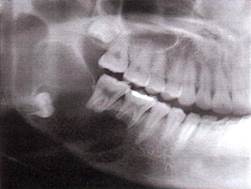

Рентгенологическая картина

Возможны следующие варианты амелобластомы:

1. Ряд округлых полостей.

2. Одна костная полость, окруженная множеством более мелких полостей.

3. Ряд округлых полостей, в 1-2 из которых заключен зубной фолликул или сфор­мированный зуб.

4. Многоугольные полости.

5. Крупнопетлистая структура кости за счет множества мелких кист.

6. Несколько единич­ных крупных кистозных полостей.

7. Одна большая кистозная полость с неровными края­ми.

8. Одна большая полость, в которую обра­щены корни зубов (напоминает радикулярную кисту).

9. Одна большая киста, в которую обра­щена коронковая часть непрорезавшегося зуба. Этот вариант напоминает фолликулярную кис­ту.

Важнейшей рентгенологической чертой адамантином является различная степень прозрачно­сти тени полостей особенно четко выраженной в поликистозных адамантино­мах. Центральные отделы кистозных полостей прозрачнее, чем краевые. В однока­мерных адамантиномах удается видеть полоску полутени вдоль костных границ опухоли. Нередко отмечается резорбция корней зубов в области опухоли.